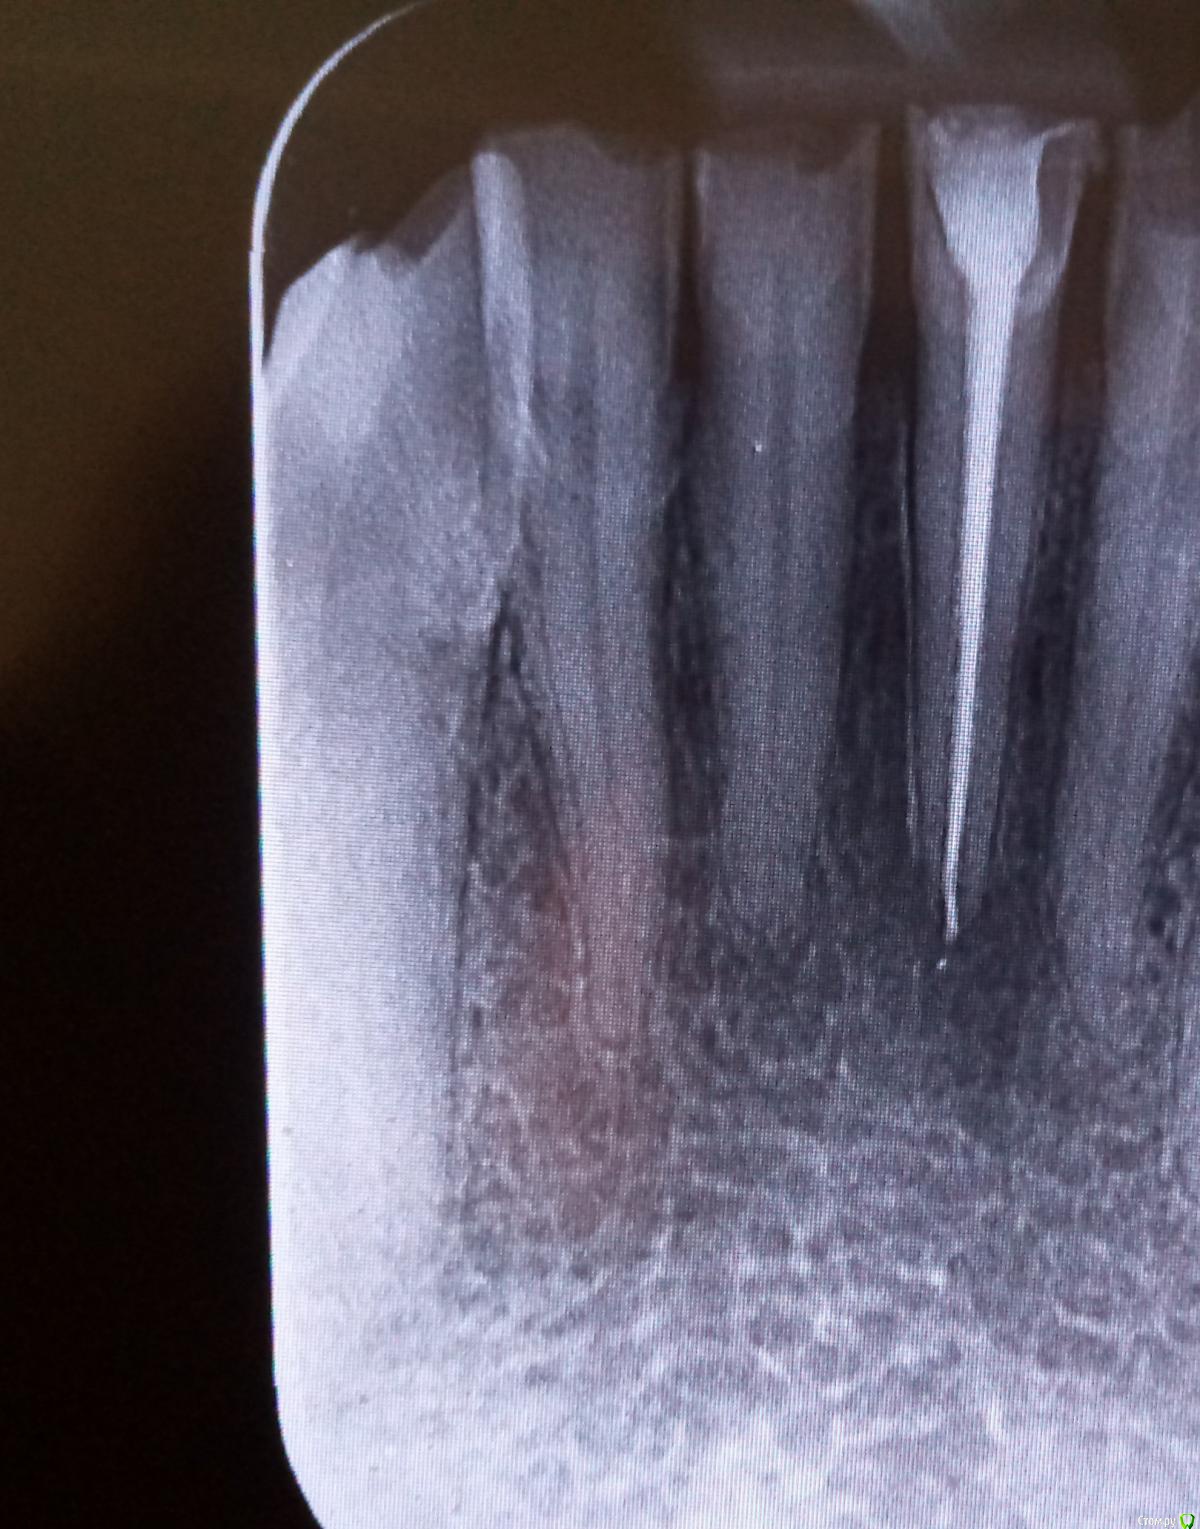

Studentic Опубликовано 6 июня, 2018 Поделиться Опубликовано 6 июня, 2018 Здравствуйте, уважаемые доктора! Очень нужен совет, как пройти канал, который раздваивается у апекса ( 31 и 32 зуб) Ссылка на комментарий

Studentic Опубликовано 7 июня, 2018 Автор Поделиться Опубликовано 7 июня, 2018 К моему большому сожалению, из-за неопытности разбил перешеек между разветвлениями. Пломбировал гуттаперчевыми штифтами, из силлеров имел только дексодент. Как вы думаете, какой прогноз на ближайшее время, учитывая что у верхушечной трети штифты следовало укомпактовать получше? Ссылка на комментарий

St. Опубликовано 7 июня, 2018 Поделиться Опубликовано 7 июня, 2018 По снимку немножко перестарались, но учитывая что зуб был витальный все должно быть хорошо. Могут быть постпломбировочные боли. Ссылка на комментарий